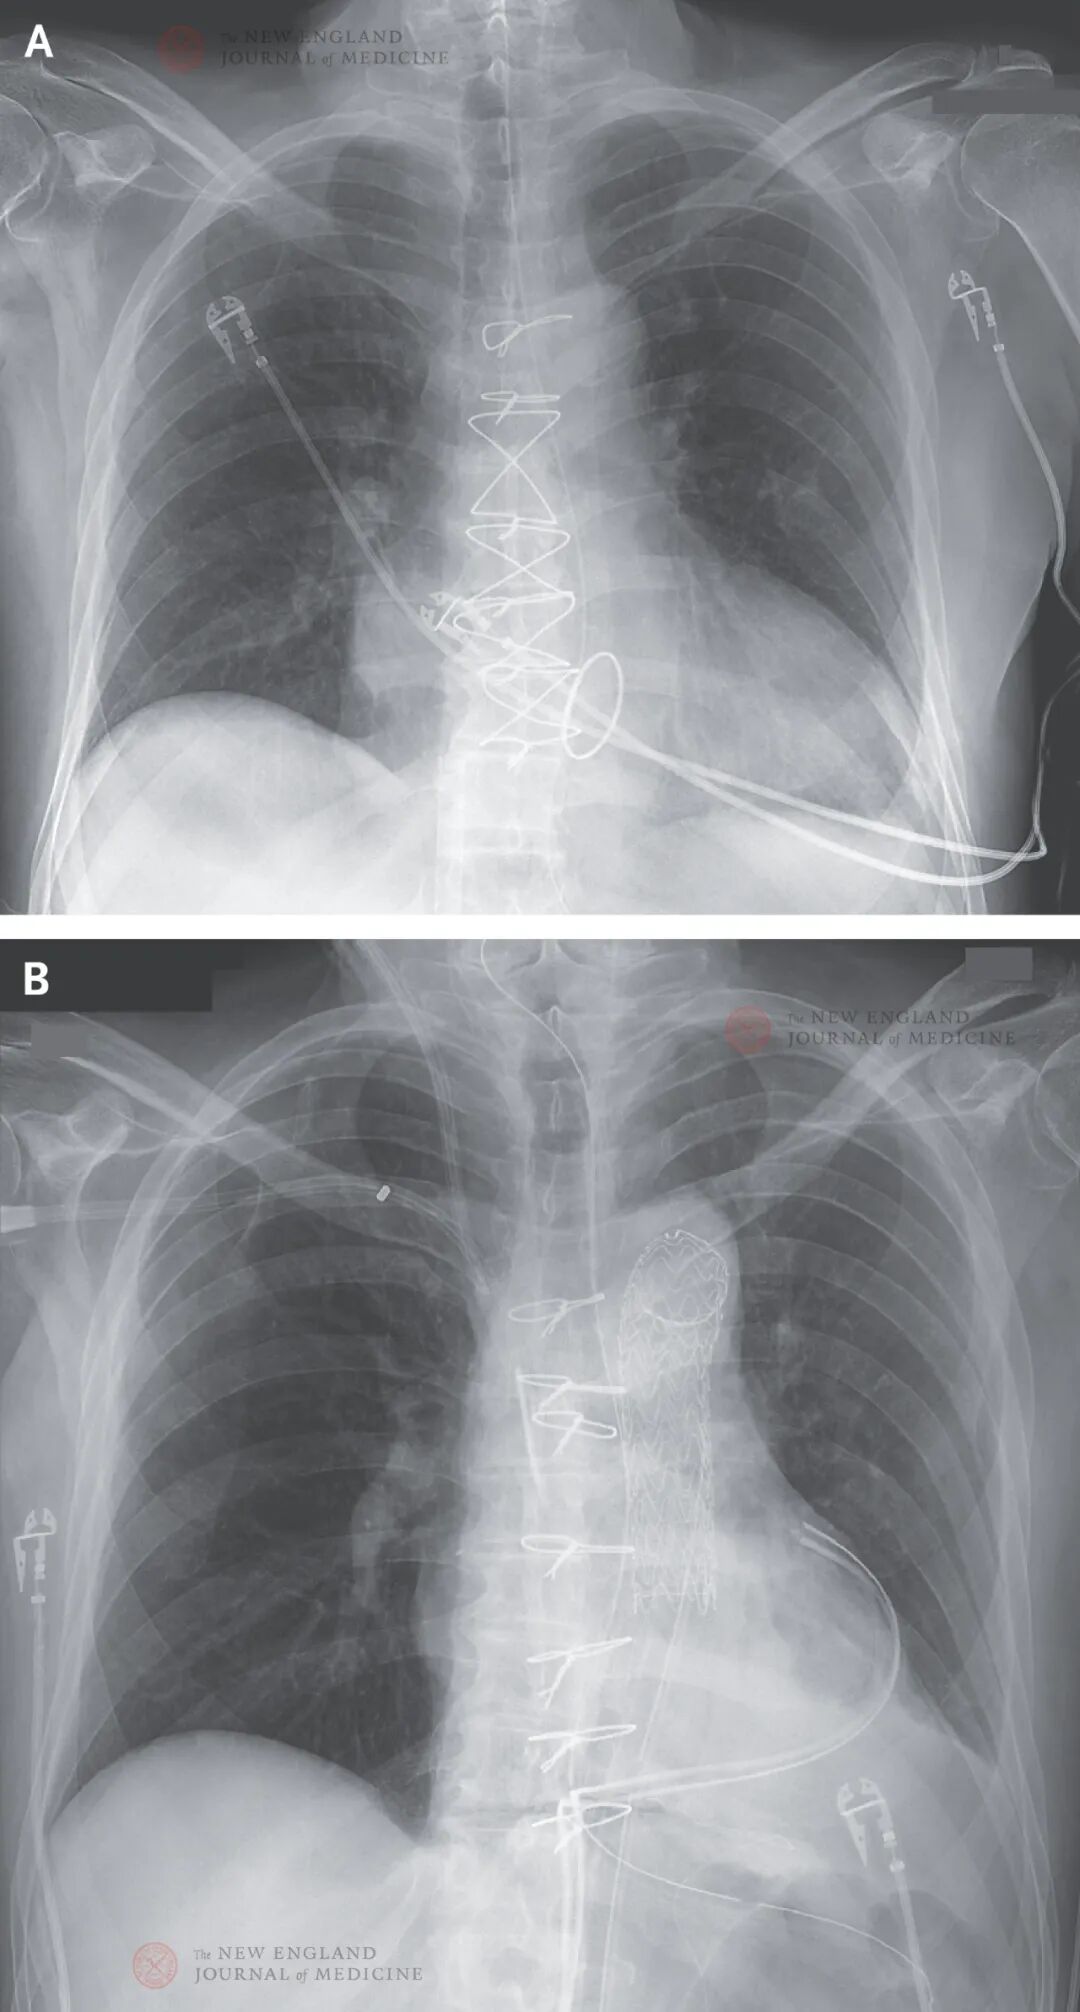

静脉-动脉ECMO(每分钟2~3升)在移植后继续,目的是支持异种移植物,减小突发室性心律失常影响。术后8小时,患者尿量减少,再次评估患者肾血流量。因残留夹层的假腔造成左肾上极动脉闭塞,放置血管内支架进行治疗。然而,少尿性急性肾衰竭在术后持续存在,导致患者需要接受肾脏替代治疗。移植后第2天,胸腔闭合后,拔除气管插管。胸片显示肺野清晰(图1)。正性肌力药一直无需使用,ECMO在第4天停止。

第6天在小剂量尼卡地平治疗下,患者血流动力学稳定,平均收缩压为130~170 mmHg,平均舒张压为40~60 mmHg;肺动脉收缩压和舒张压分别为32~46 mmHg和18~25 mmHg,中心静脉压为6~13 mmHg。心输出量为每分钟5.0~6.0升,每搏输出量为每平方米体表面积65~70毫升。异种移植物保持每分钟70-90次的窦性心律。LVEF至少为55%。

移植后第43天,患者变得更加嗜睡,给予气管插管;患者出现低血压,经过补液和血管升压素治疗后有效。胸片提示双肺进展性渗出。支气管镜检查显示右肺一级和二级气道遍布弥漫性浅溃疡,提示患者发生病毒或真菌感染。患者患低丙种球蛋白血症。扩大抗微生物剂覆盖范围,并且静脉注射1 g/kg剂量免疫球蛋白。每周mcfDNA检测结果显示pCMV明显增加,这令人担心可能发生病毒感染。

剖腹探查未见异常。新放置的肺动脉导管显示混合静脉血氧饱和度为33%。虽然超声心动图显示LVEF为65%~70%,但左心室壁厚度和右心室壁厚度显著增加,左心室腔显著减小(图2B)。